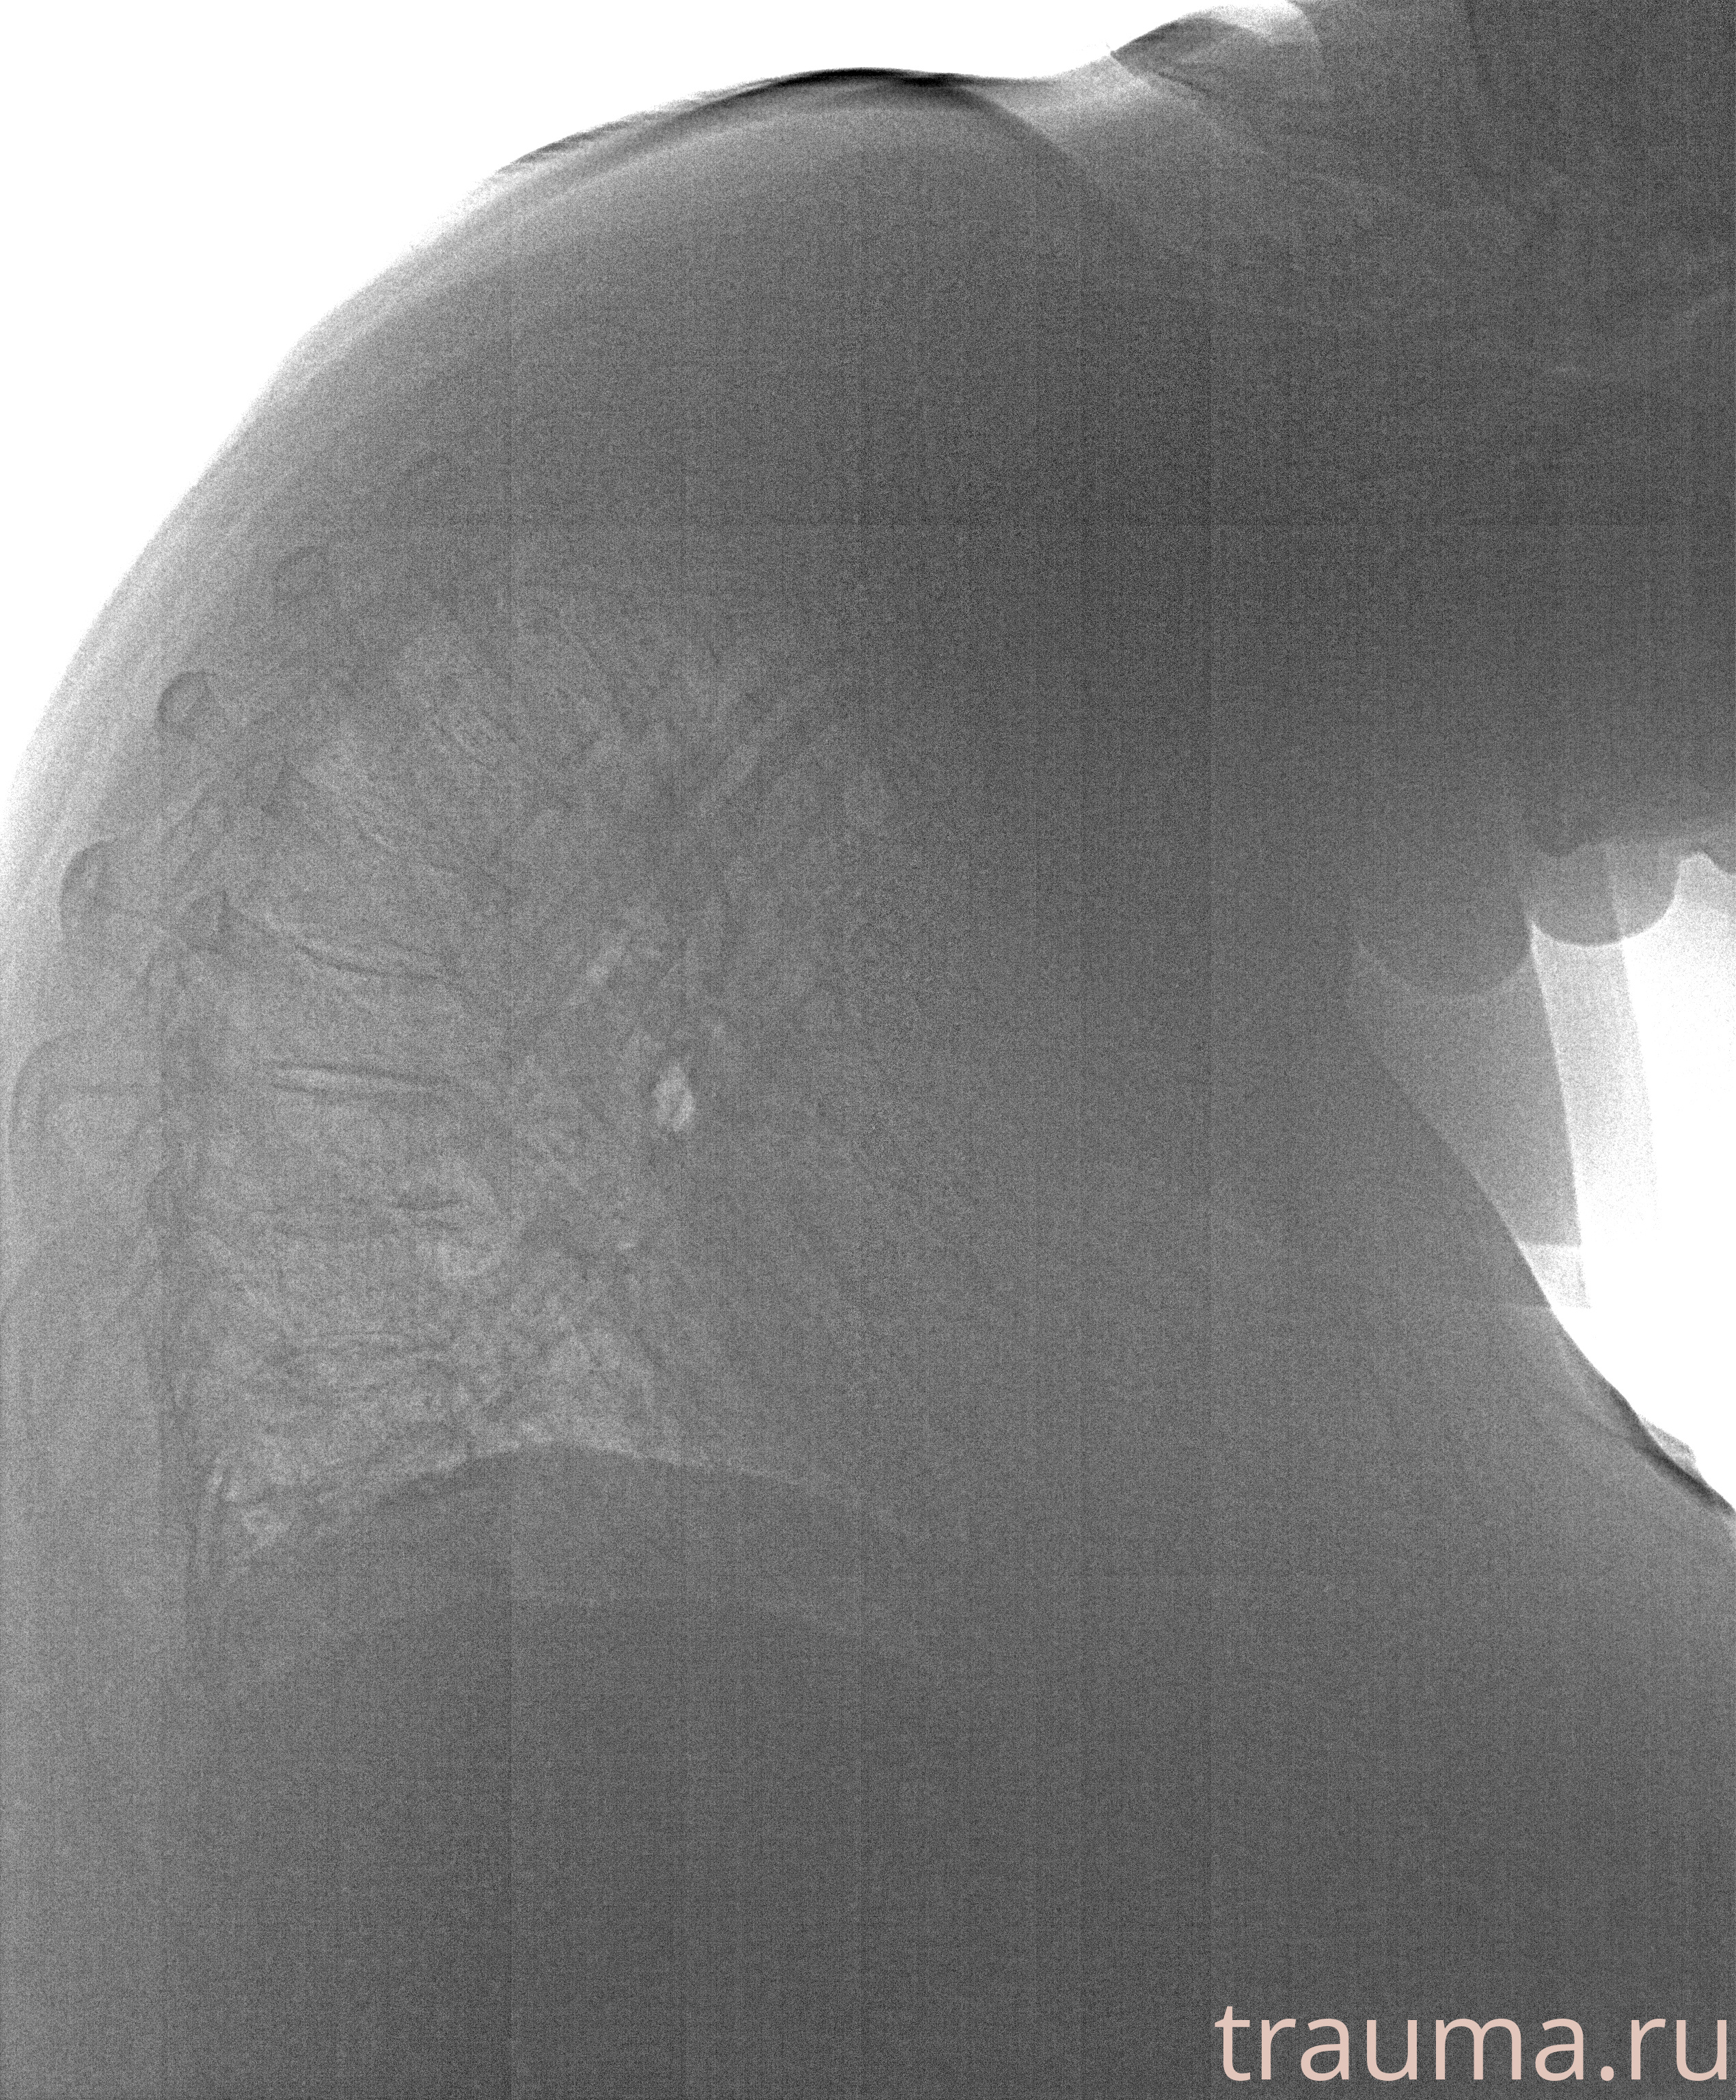

Рентген на дому: по вашему адресу приезжает врач-рентгенолог, травматолог-ортопед с мобильным рентгеновским аппаратом, проводит диагностику травмы или заболевания, делает необходимые рентгенограммы, дает рекомендации по дальнейшему лечению. Получить качественные снимки в домашних условиях возможно благодаря уникальной методике, разработанной МосРентген Центром для института  Склифосовского